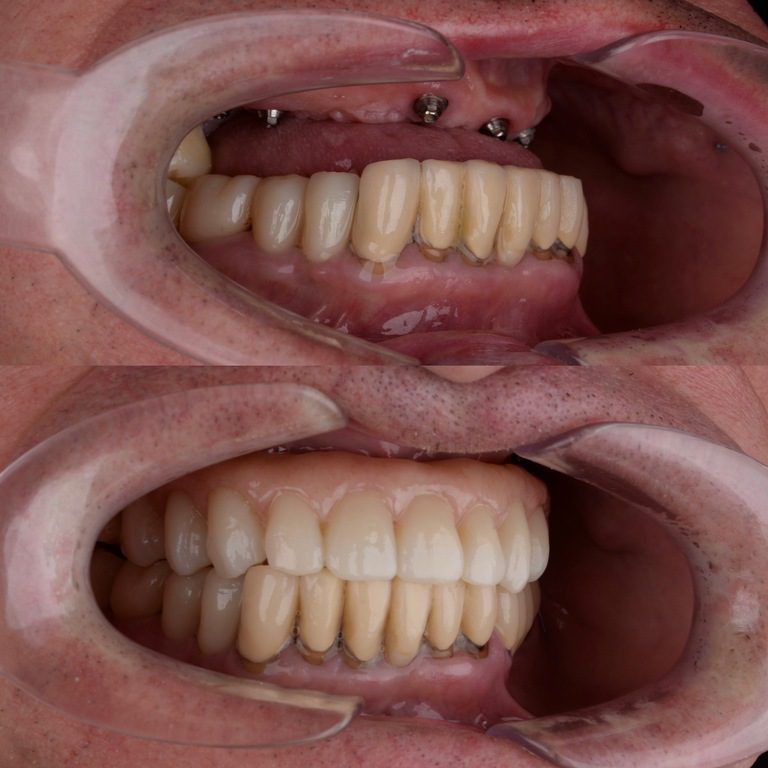

- put in implants or prosthetics that come off

PROSTHETICS

Restore a tooth or a whole line of them with help of modern methods and high quality materiel

SURGICAL DENTAL WORK

Remove teeth, we carry out plastic surgery of soft and bone tissues, install imlpants and other